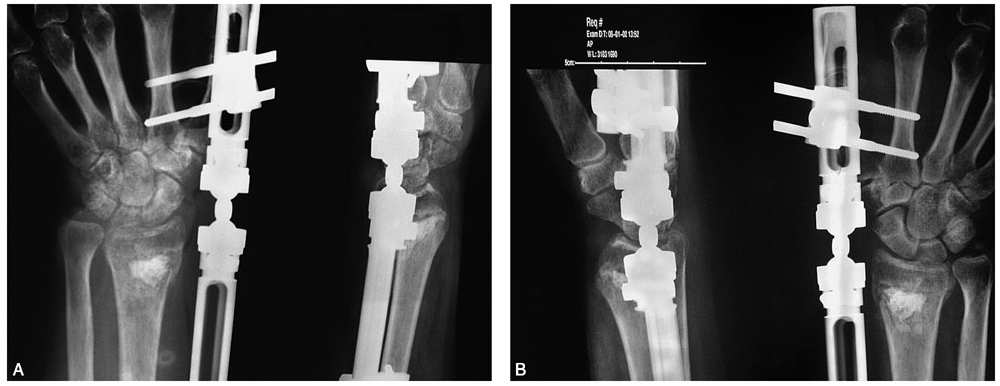

术前拍腕关节正、侧位X线片,腕关节冠状位、矢状位和水平位CT(图2-2)此患者骨缺损和无法闭合复位的骨片均在背侧,宜采用背侧入路,复位,植骨,固定。取患肢前臂远端桡背侧纵切口(图2-3)从伸拇长肌腱和桡侧伸腕长、短肌之间进入,注意保护血管神经和肌腱,显露清理折端骨缺损区域和背侧移位的骨片(图2-4复位,植骨,外固定架超关节固定(图2-5、图2-6)。术中透视骨折复位固定满意(图2-7),术后拍X线片证实(图2-8)。此手术的优点在于避免了局部存在内固定物的刺激,避免二期切开取出固定物所致的再次损伤。

图2-5 外固定架超关节固定

图2-6 显示植骨和骨片复位

图2-7 术中透视示骨折复位、固定、植骨满意

图2-8 术后X线片示骨折复位、固定、植骨满意